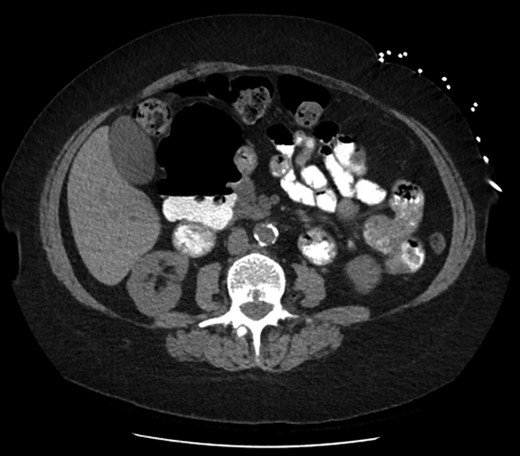

On examination she was afebrile, with observations within the normal parameters. Her abdomen was tender with voluntary guarding in the epigastrium. Her initial blood tests were all normal other than mildly increased inflammatory markers. She underwent a non-contrast (due to chronic kidney disease) Computed Tomography (CT) scan that revealed no evidence of acute biliary/gallbladder disease, however there was the appearance of a large duodenal diverticulum. The patient was recalled for an oral contrast study that confirmed a giant duodenal diverticulum arising from the second/third part of the duodenum measuring 9.5 × 5.7 × 7.3 cm. There were no signs of surrounding inflammation or pending rupture and this was thought to be an incidental finding. Upper abdominal ultrasound revealed no acute biliary tract disease. Her pain settled and she was discharged home.

On retrospective analysis of prior scans (CT and Magnetic Resonance Imaging (MRI)) of this woman there was evidence of this duodenal diverticulum for over five years and previous OGD three years prior had noted two duodenal diverticula; one small and one large. The patient denied previous knowledge of these findings (Fig 1 and 2).

Sagittal slice of computed tomography (CT) scan—giant duodenal diverticulum partly filled with oral contrast. The arrow is indicating the neck of the diverticulum.